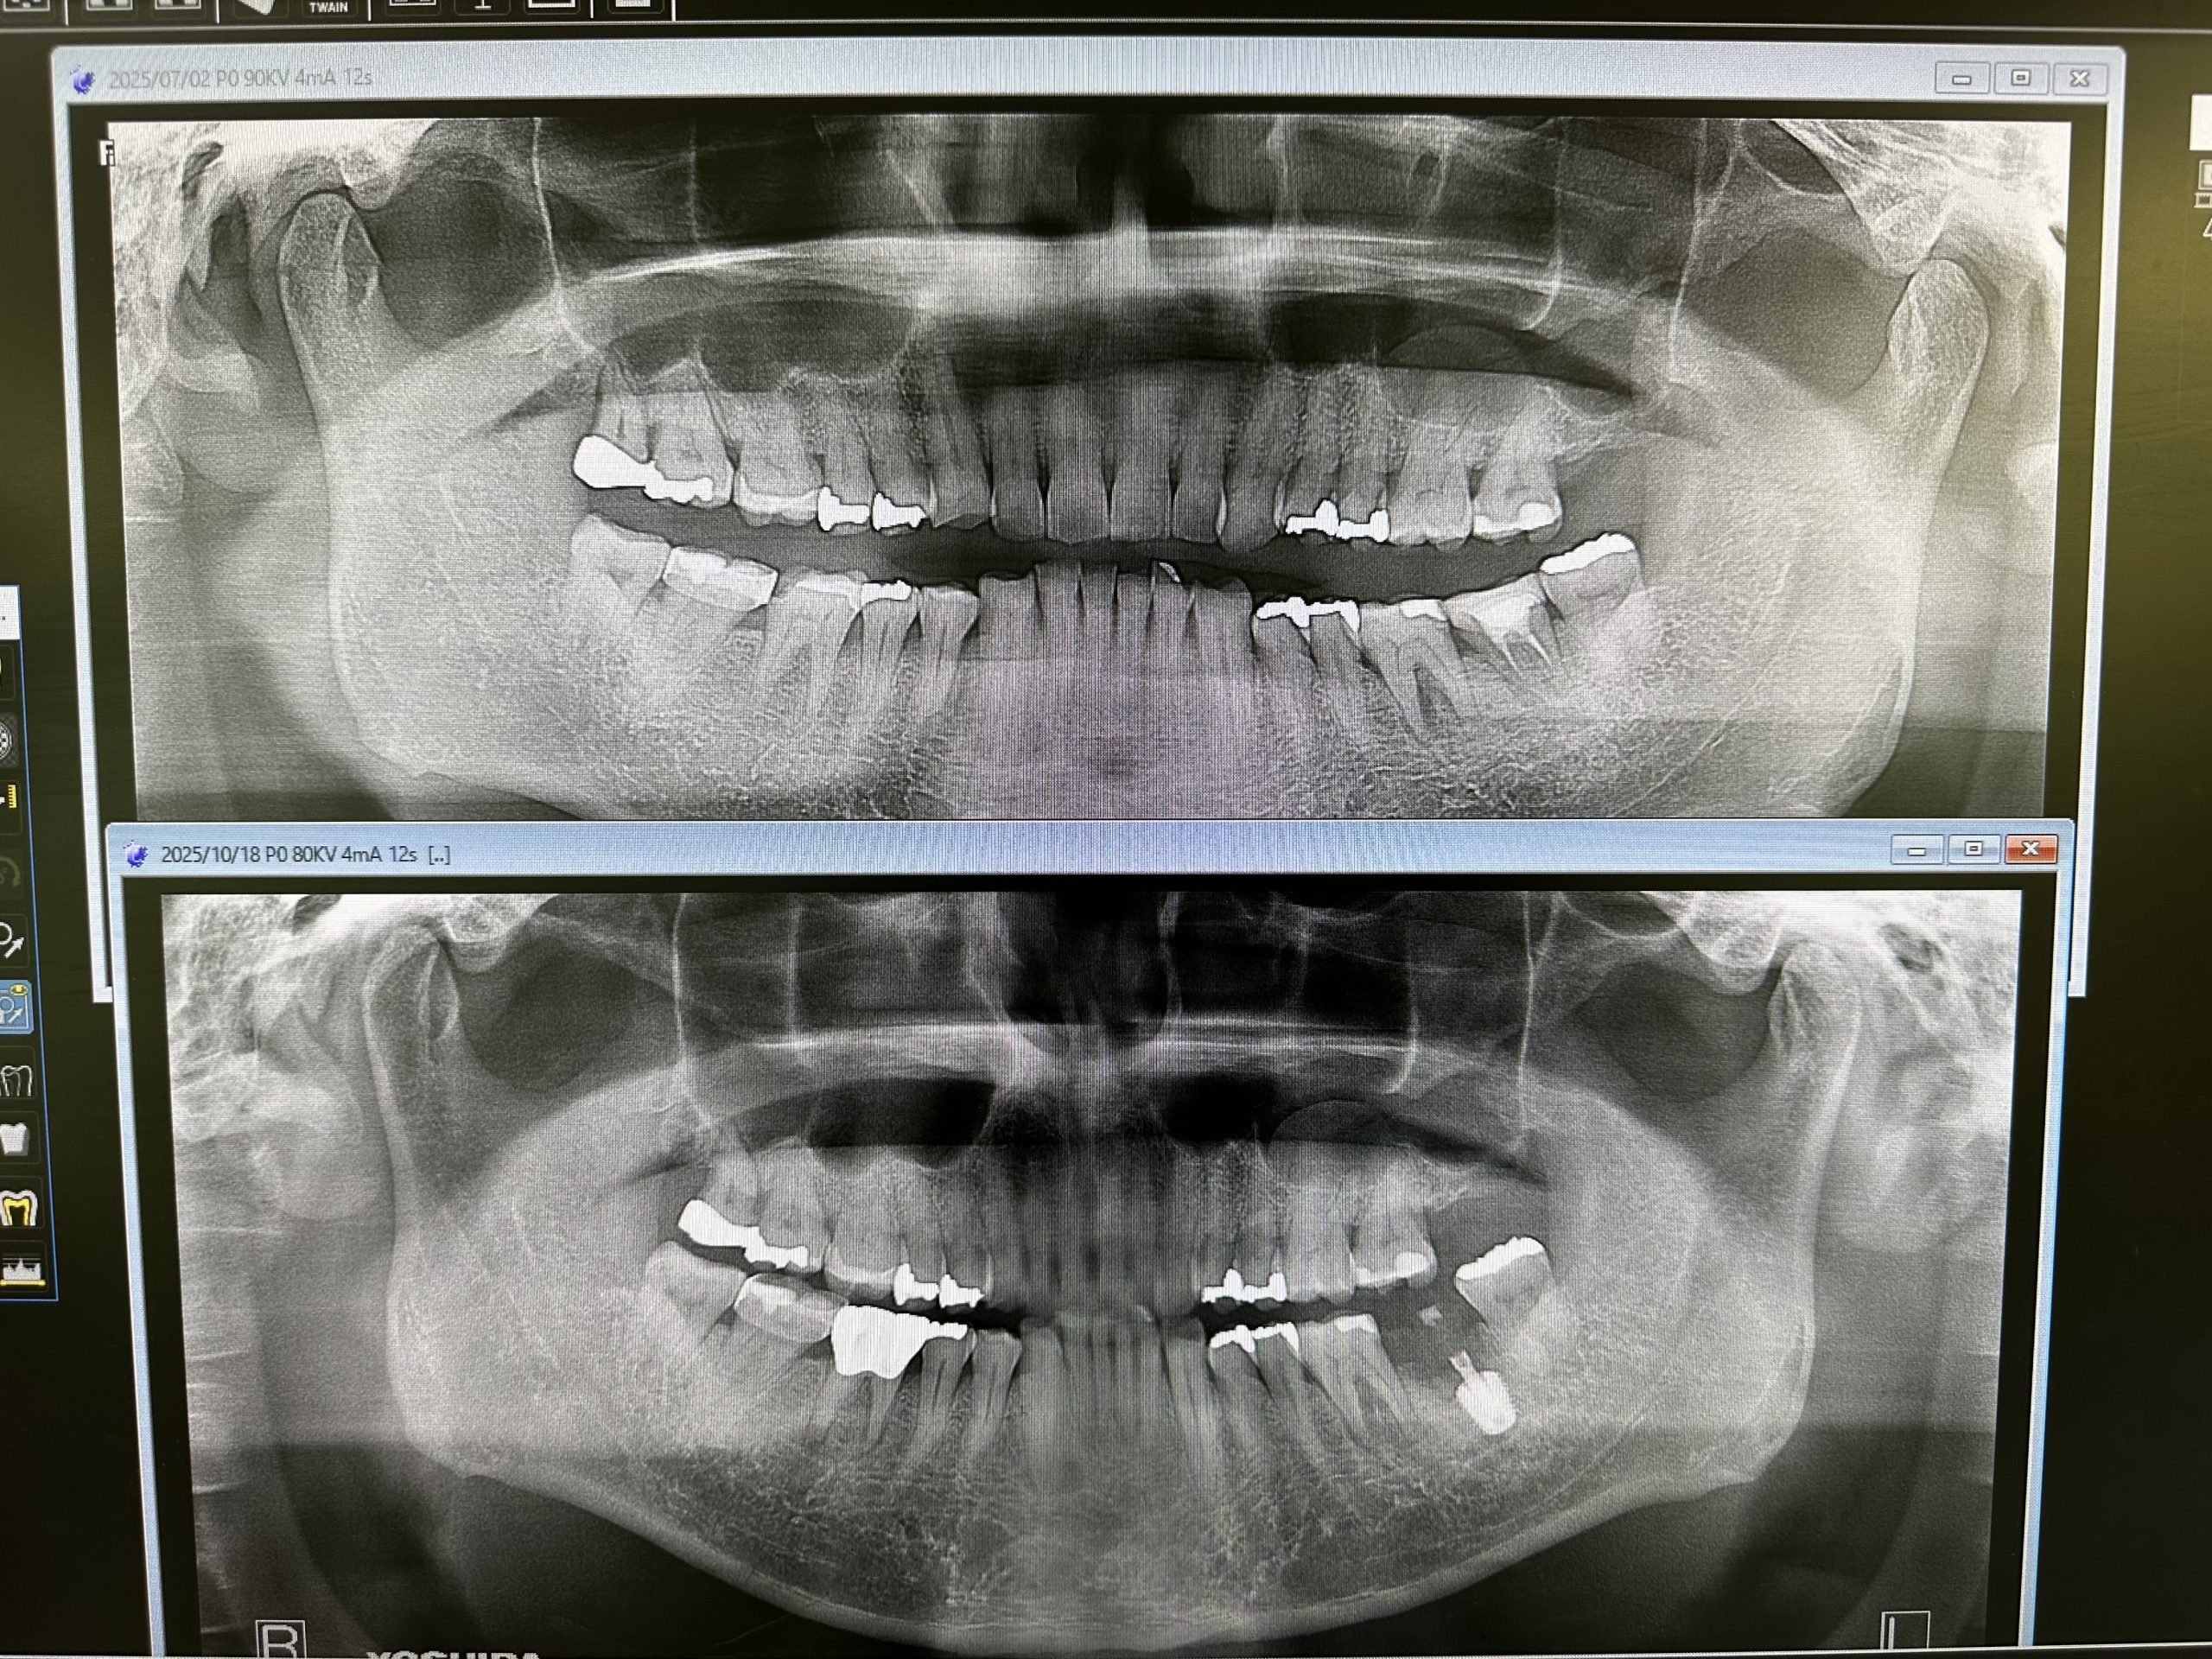

土曜日、本日は2件オペ

御二方共に一本のみ、抜歯即時に成熟埋入

結果20分から30分で終わり、ストレスなし

計測値も良く6w後には仮歯印象だね